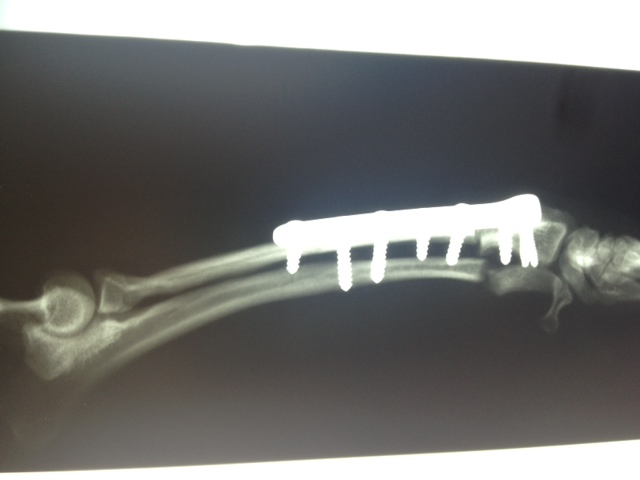

Heute hatte Felipa ihren ersten OP-Termin.

Wir waren alle sehr aufgeregt. Und selbst der erfahrene Arzt meinte, es sei eine ungewöhnliche Aktion, denn normalerweise weist nur ein Pfötchen so starke Anomalien auf. Er hatte es noch nicht, dass beide operiert werden müssen.

In sechs Wochen erfolgt dann die zweite OP.